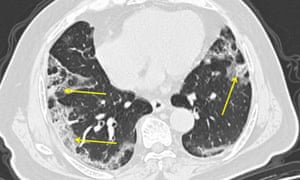

Wilson says there is evidence that pneumonia caused by Covid-19 may be particularly severe. Wilson says cases of coronavirus pneumonia tend to affect all of the lungs, instead of just small parts.